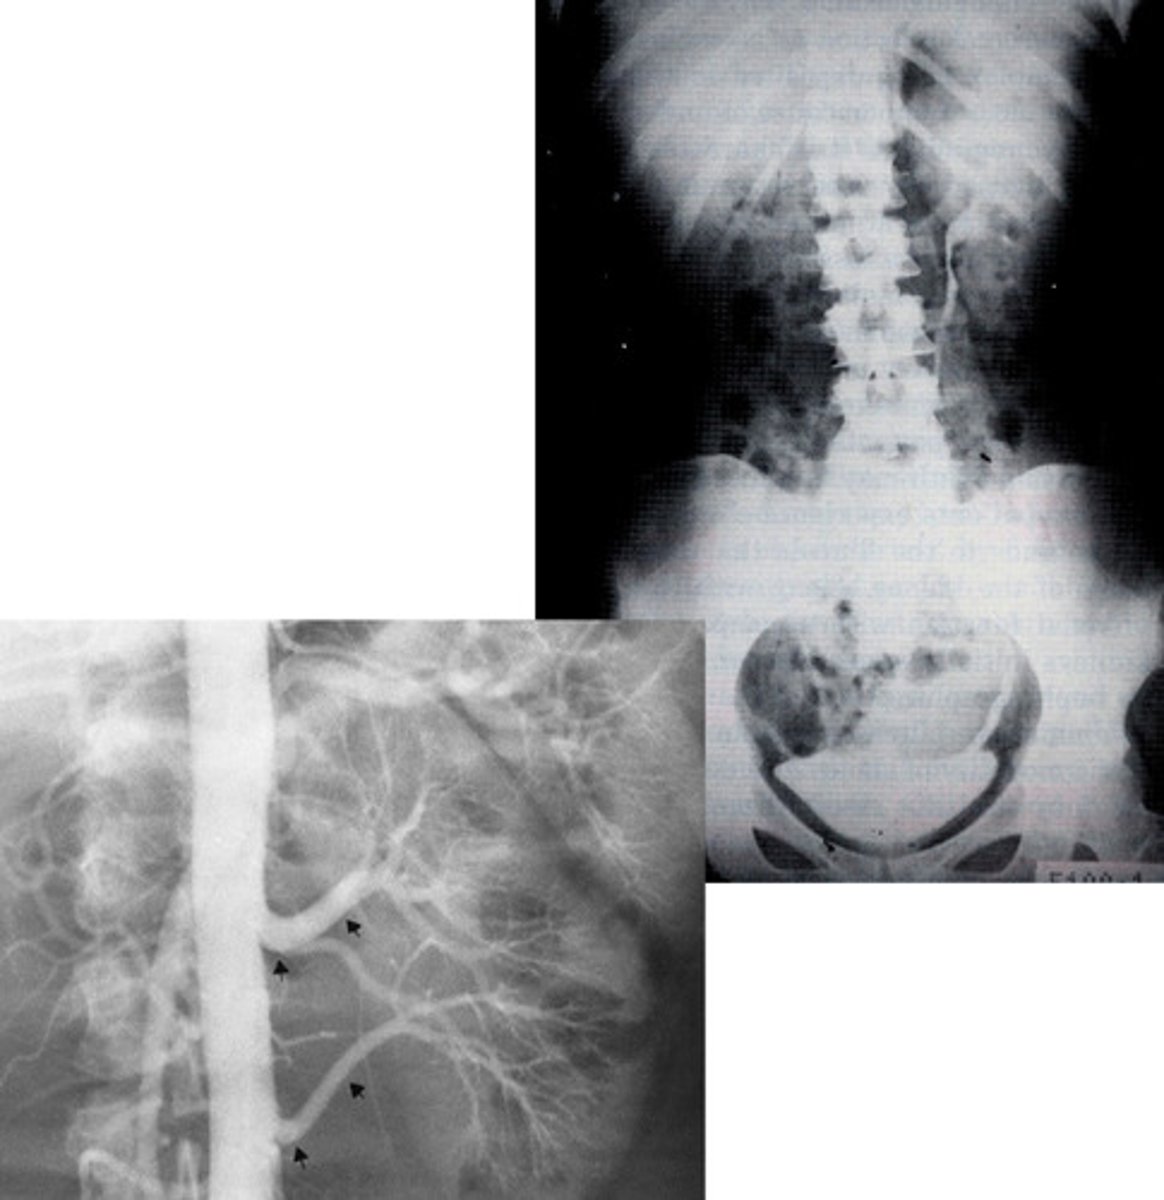

- Horseshoe Kidney

- Kidney stones

- What congenital anomaly occurs when the lower poles of the kidney fail to separate in the fetus and results in a horseshoe-shaped kidney?

- What can patients frequently develop because the ureters are displaced with this pathology?

- Wilms Tumor / Nephroblastoma

- What type of renal neoplasm arises from the embryonic renal tissue that distorts the calyces and creates a vine like blood supply?

- This is the most common abdominal neoplasm in who?